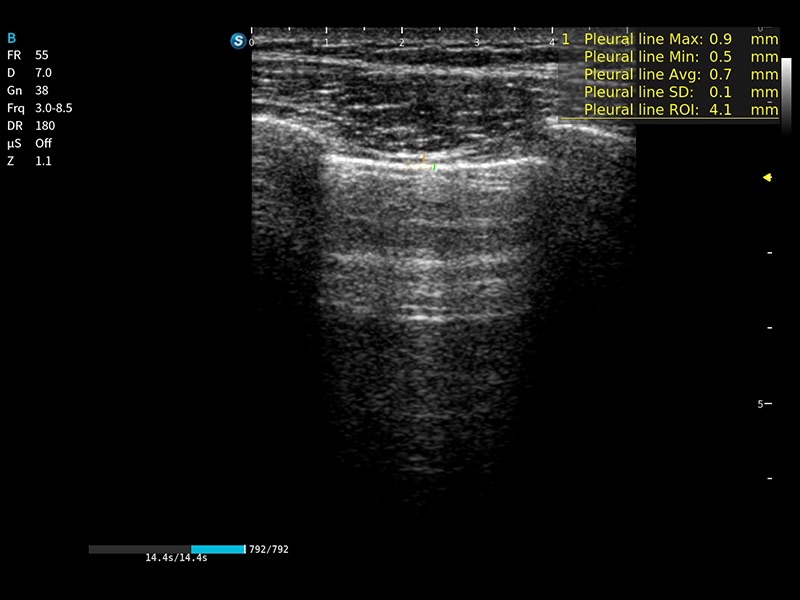

E11搭载了丰富的自动化测量工具,以及专为POC科室定制的高级功能;同时配备了为急诊医师量身打造的 SonoFast急重症超声流程,以帮助临床医生最大限度的提升工作效率